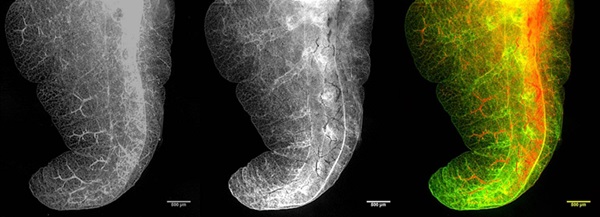

Scanning laser optical tomography (SLOT), which LZH describes as the optical equivalent of the computed tomography (CT) scan, generates images with the same resolution in all three spatial planes.

Capable of simultaneously recording transmitted, scattered and fluorescent light, LZH claims that SLOT can quickly generate three-dimensional images with a resolution better than one-thousandth of the target object's size.

Using intrinsic optical contrast processes, such as absorption, LZH says that it is possible to generate high-resolution ex vivo volumetric images of large samples, for example locust heads or mouse lungs. Using absorption and auto-fluorescent imaging, researchers at the center are also said to have generated images of lung structures showing resolution of individual alveolae.